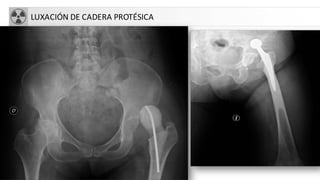

LUXACIÓN DE CADERA PROTÉSICA

LUXACIONES DE CADERA

CLASIFICACIÓN:

• Posteriores (75%)

-Iliacas o altas (las mas frecuentes)

-Isquiáticas o bajas

• Anteriores (25%)

-obturatrices

-Pubianas